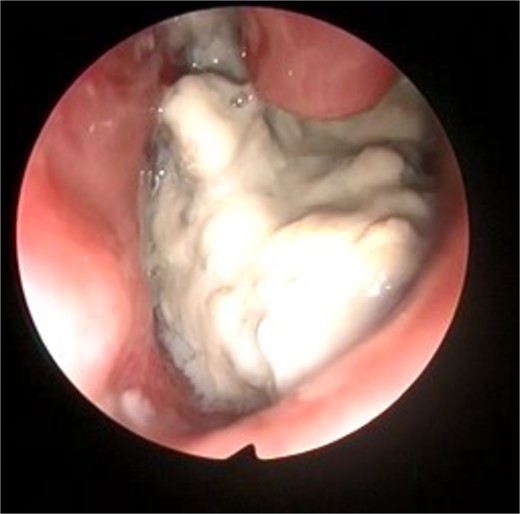

This presentation was clinically suggestive of left-sided rhinolith. Hence, a CT scan was obtained, which showed a well-defined expansile heterogeneous calcified/ossified lesion occupying the inferior aspect of the left nasal cavity measuring 2.5 × 3 × 2.1 cm (craniocaudal × anteroposterior × transverse). Also, the lesion was expanding the nasal cavities with bone remodeling of the medial wall of the maxillary sinus with remodeling and superior displacement of the left inferior turbinate (Fig. 1). These findings were highly suggestive of rhinolith; therefore, the patient was scheduled for a left endoscopic rhinolith removal. Intraoperatively, a giant, calcified nasal lesion was noticed and removed from the left nasal cavity, which was attached to the inferior and middle turbinates (Fig. 2). Furthermore, a biopsy from the lesion was taken for histopathological analysis, showing calcification with fibrin and hemorrhage. These findings confirmed the diagnosis of left nasal rhinolith, and the patient was discharged with no complications. Six months after the procedure, A the patient presented to the clinic with no signs of recurrence, and her endoscopic examination revealed clear nasal cavities (Fig. 3).

Intraoperative left nasal endoscopic view showing a whitish mass lying under the floor of the inferior turbinate.